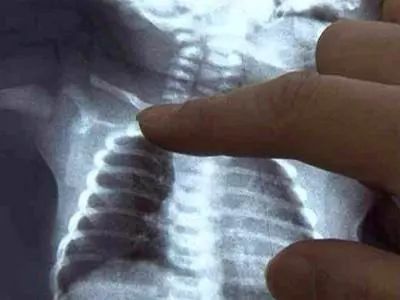

新生小孩锁骨骨折怎么办?新生儿锁骨骨折是新生儿娩出过程中最常的骨折。新生儿锁骨骨折治疗简易,预后良好,没有并发症,故不应采取任何过激的治疗方法新生婴儿的锁骨骨折,大多数是产伤,而且几乎都是顺产的,这种骨折比较常见。

有些出生后,家人并不知道锁骨发生骨折,只是骨折的这一边手臂活动比较少,引起雷注意,一拍片,才发现有骨折。有的是给孩子洗澡穿衣服的时候,孩子哭泣,另一边则没有这样的情况,引起家人都注意,才发现的。

也有的家长比较细心,看见锁骨的地方两边不一样,一边明显鼓起来,摸或者按压会引起孩子哭闹挣扎,引起注意,去拍片才发现有骨折。

新生儿锁骨骨折恢复较快,一般都于骨折的一个礼拜出现骨膜增生及骨痂形成,两年内随着小儿的生长发育,肩部增宽,锁骨的畸形均可自行消失,完全恢复原状,不会留有后遗症。

一般在10天左右,就会愈合,不需要任何治疗。虽然对位对线不好,愈合后有个鼓起来的包包,硬硬的,以后会慢慢塑形,包包会逐渐消失。所以是不需要担心的。